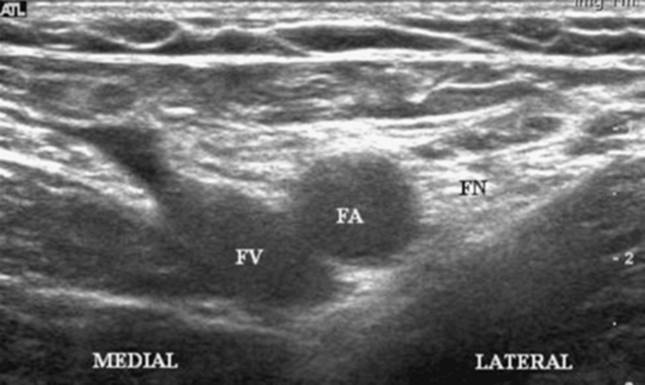

Technique: Sterile prep of the skin. The probe is placed just below the inguinal crease with the probe oriented in the axial plane. The femoral artery is identified and the hyperechoic nerve is identified lateral to the artery (Fig. 39-3). The needle is inserted at the lateral edge of the probe and advanced until a contraction is seen in the quadriceps femoris muscle. A stimulating current of 0.5 mA is usually appropriate to elicit a contraction (Fig. 39-4). Injection of local anesthetic proceeds until the nerve is surrounded by a hypoechoic ring (Fig. 39-5).

Figure 39-5. Injection of local anesthetic until the nerve is surrounded by a hypoechoic ring.